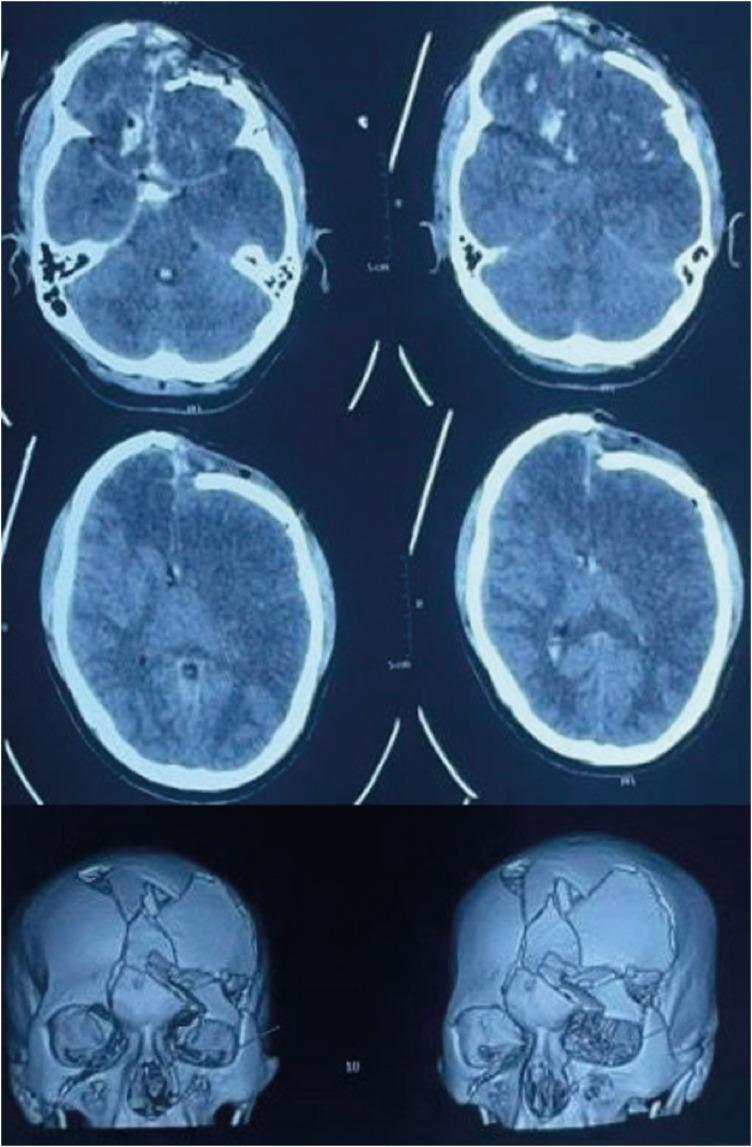

Farm-related head injuries are a significant cause of death and disability in rural households. Traumatic brain injury can result in long-term disability. The use of modern farming equipment has increased in the Indian agricultural sector over the last few decades. Machines such as threshers and winnowing devices can cause open skull fractures or scalp avulsions, while the fall of heavy tools may lead to severe head trauma. Farm animals such as bullocks and horses can also inflict traumatic brain injuries with their pointed horns, through trampling, kicking, or rarely biting. We present a case series of four patients who sustained head injuries due to farm-related accidents. All patients sustained compound cranial fractures with underlying brain parenchymal injuries, and three of them achieved complete recovery following timely medical intervention.

与农场相关的头部损伤是农村家庭死亡和残疾的一个重要原因。创伤性脑损伤可导致长期残疾。在过去几十年里,印度农业部门现代农用设备的使用有所增加。脱粒机和扬谷设备等机器可导致开放性颅骨骨折或头皮撕脱伤,而重型工具掉落可能导致严重的头部创伤。公牛和马等农场动物也可能用它们的尖角、通过踩踏、踢踹或极少情况下的撕咬造成创伤性脑损伤。我们报告了一系列4例因与农场相关的事故而头部受伤的患者。所有患者均发生复合性颅骨骨折并伴有潜在的脑实质损伤,其中3例经及时医疗干预后完全康复。